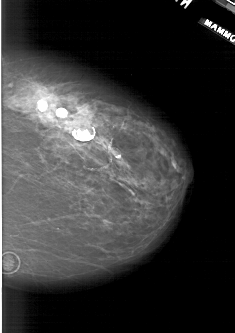

A_1941_1.RIGHT_CC

RIGHT_CC LINES 5326 PIXELS_PER_LINE 3751 BITS_PER_PIXEL 12 RESOLUTION 43.5 NON_OVERLAY